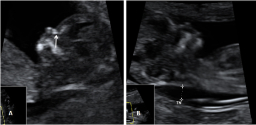

Ecografía de la semana 12

Los motivos por los que los ginecólogos recomiendan realizar una ecografía en la semana 12 de embarazo tienen que ver con el desarrollo anatómico y el tamaño del feto: ahora es lo bastante grande para comprobar si presenta anomalías. Además, ya se puede ver con claridad si hay uno o dos (o tres) bebés, calcular  la fecha probable de parto teniendo en cuenta la edad gestacional, y confirmar que esta coincide con el desarrollo del bebé. Se puede medir el llamado pliegue nucal (si sobrepasa unos parámetros a veces es indicio de problemas cromosómicos) y, si el bebé se deja, conocer su sexo.